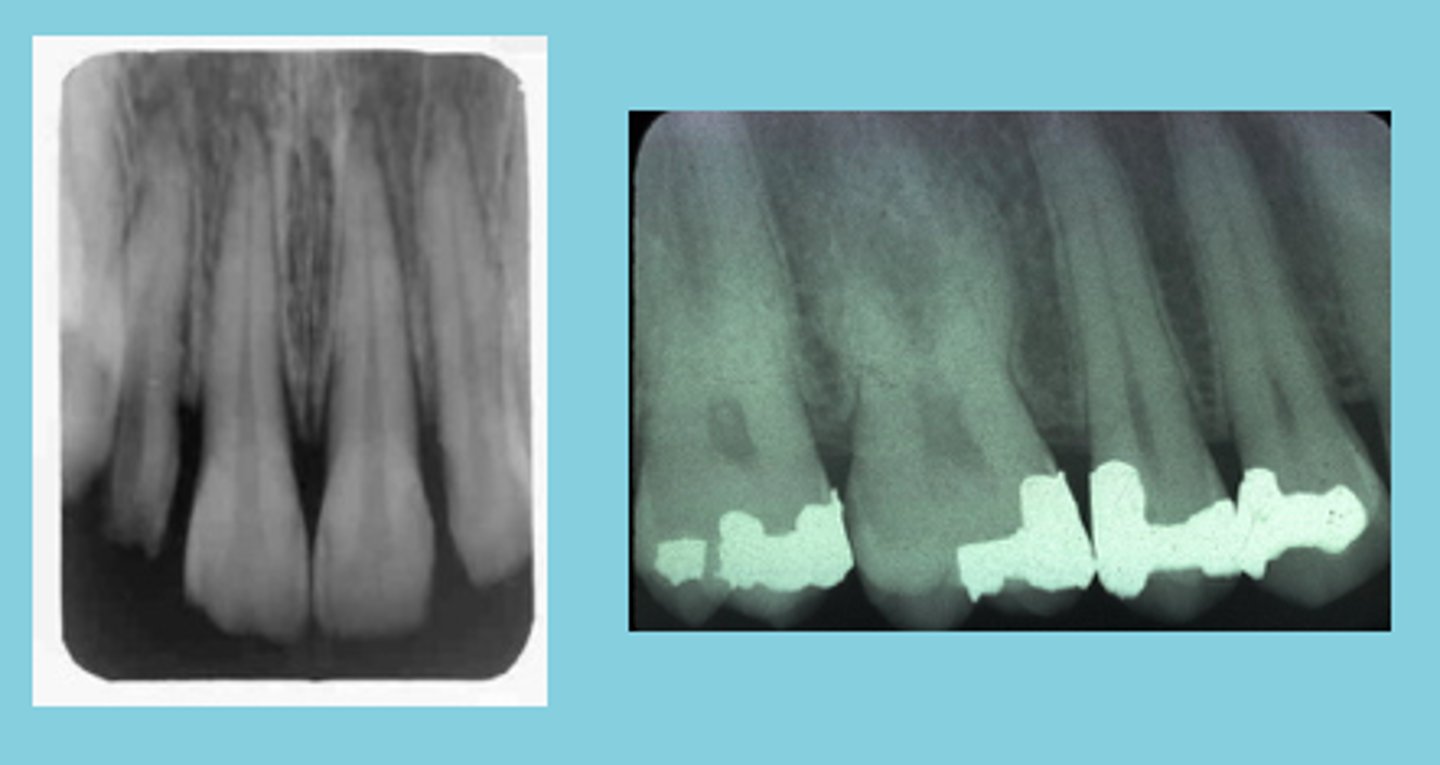

Foreshortened image

results from excessive vertical angulation

Elongated images

results from insufficient vertical angulation

Correct vertical angulation

Results in a radiographic image that is the same length as the tooth

Incorrect vertical angulation

Results in a radiographic image that is not the same length as the tooth